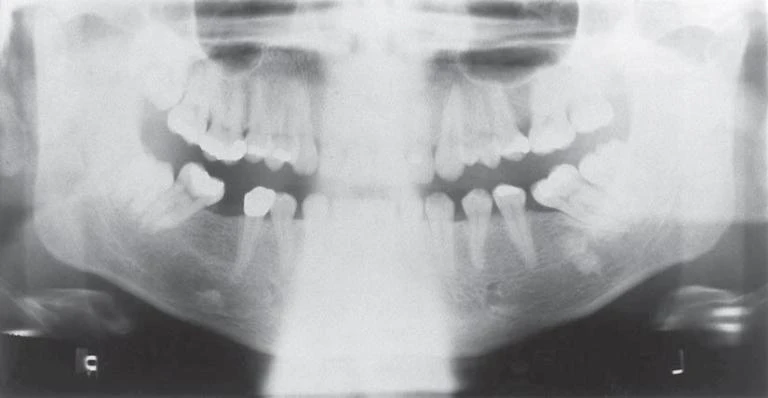

Vị trí cổ đúng cách được thực hiện tốt nhất bằng cách đặt một lực dựng nhẹ lên phần nhô của xương chẩm khi điều chỉnh vị trí đầu. Để bệnh nhân cúi đầu và hướng cổ về phía trước tạo nên một hình ảnh mờ đục lớn trên đường giữa do hiện tượng chồng cấu trúc của khối cột sống cổ. Bóng này che đi toàn bộ vùng giữa của xương hàm dưới và có thể cần chụp phim lại. Cuối cùng, sau khi bệnh nhân được điều chỉnh vị trí chụp, nên hướng dẫn bệnh nhân nuốt và giữ lưỡi tại trần miệng. Điều này nâng phần lưng lưỡi lên khẩu cái cứng, loại bỏ phần không gian trống và cho hình ảnh tối ưu vùng chóp chân răng hàm trên.